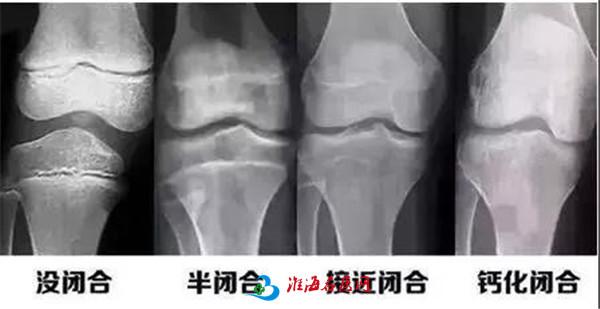

人的生长发育的程度可以用两个年龄来表示,即生活年龄(日历年龄)和生物年龄(骨龄)。

而骨龄和儿童身高之间有着密切的关系,通过骨龄可以及早了解儿童的生长发育潜能以及性成熟的趋势,还可预测儿童的成年身高。